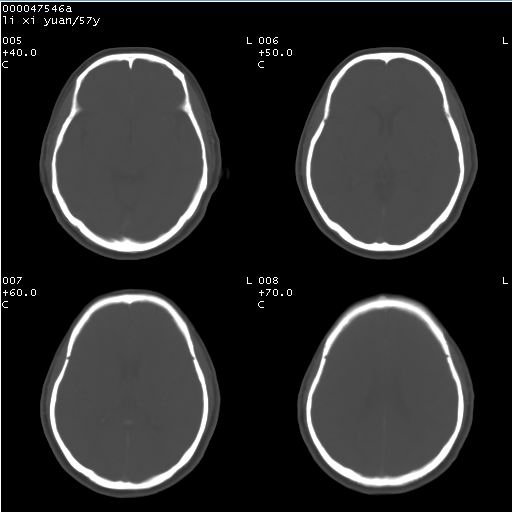

以下是引用余辉在2008-4-27 14:02:00的发言:[br]病灶位于中央沟前方?位于额叶?高密度灶,灶周水肿不明显,病灶似沿脑沟走行,强化明显,局部层面呈现环状强化,考虑1脑表面血管性疾病,如血管瘤,血管扩张,灶内血栓形成,其次考虑肿瘤如脑膜瘤、转移瘤,胶母等

以下是引用形影不离在2008-4-27 14:13:00的发言:[br]考虑胶质瘤可能性大,不排除慢性炎性肉芽肿。建议mri检查。